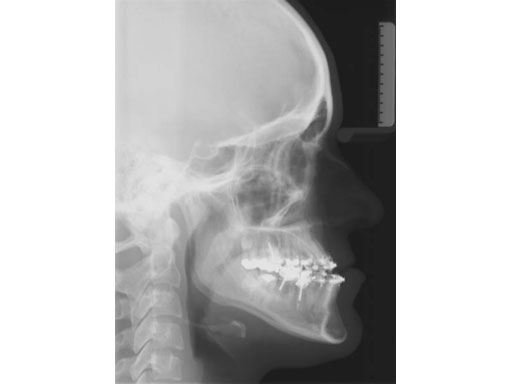

Lefort I maxillary osteotomy, bilateral sagittal osteotomies, and a genioplasty, all fixed with matrix orthognathic system used in a 19-year-old female with significant skeletofacial deformity including maxillary hypoplasia, mandibular excess, and laterognathia.

Fig 1a-c Preoperative images.